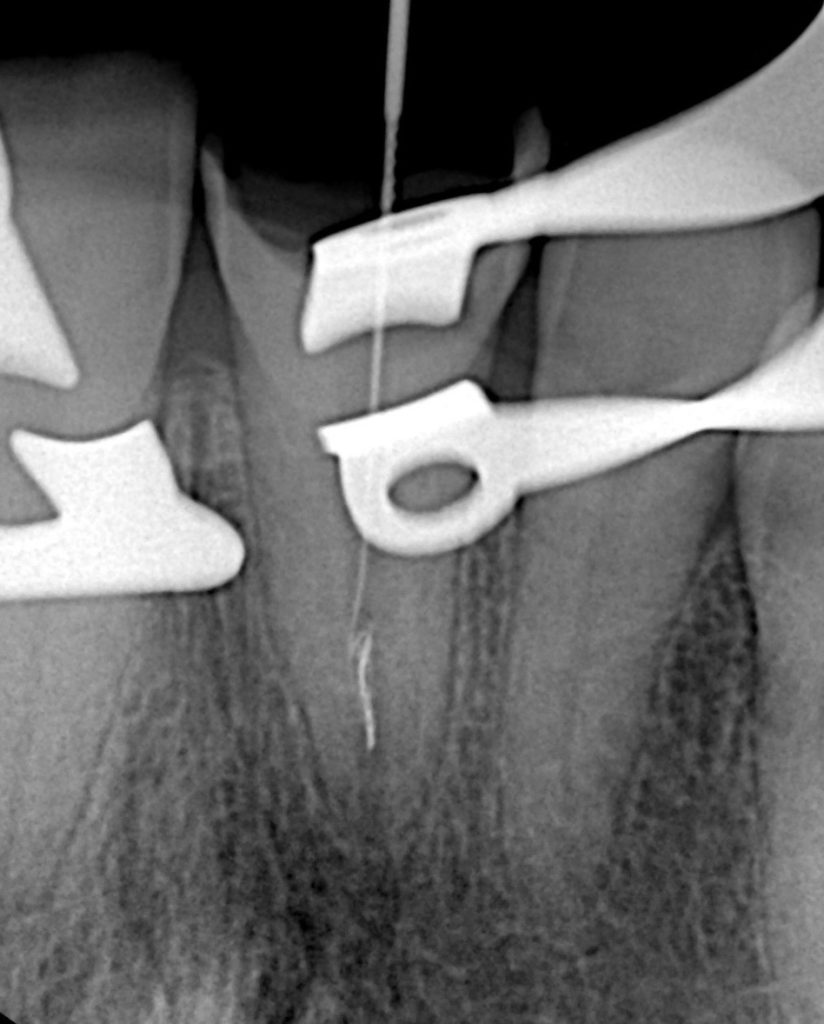

Clinical exam revealed a coronal fracture exposing previous access and visible sealer remnant. Periapical radiograph confirmed a metallic fragment lodged in the apical third with a faint radiolucency (Fig 1–2).

The fragment was localized using ultrasonic tips (ET20, Satelec) under 20× magnification. Troughing around the coronal end loosened the fragment, which was retrieved atraumatically using the braiding technique with micro-files (Fig 5–6).

Patency was re-established with a #10 K-file to full working length, confirmed radiographically.